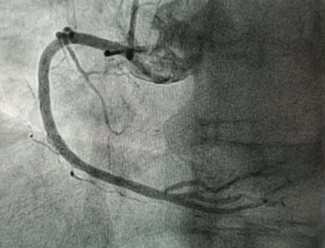

A 66-year-old male presented with ST-segment elevation myocardial infarction. Emergent coronary angiography showed thrombotic occlusion of the distal right coronary artery (RCA). Percutaneous coronary intervention (PCI) of the culprit RCA...